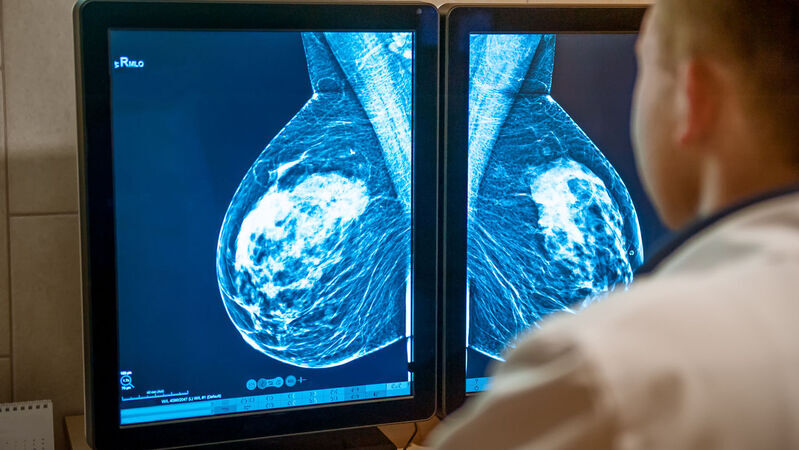

I risultati dello studio Destiny evidenziano l’importanza di determinare con precisione lo stato di Her2.

In questo senso, è fondamentale il ruolo del team multidisciplinare nei centri di senologia, in particolare la collaborazione tra oncologo e patologo che effettua i test diagnostici per definire il profilo molecolare.